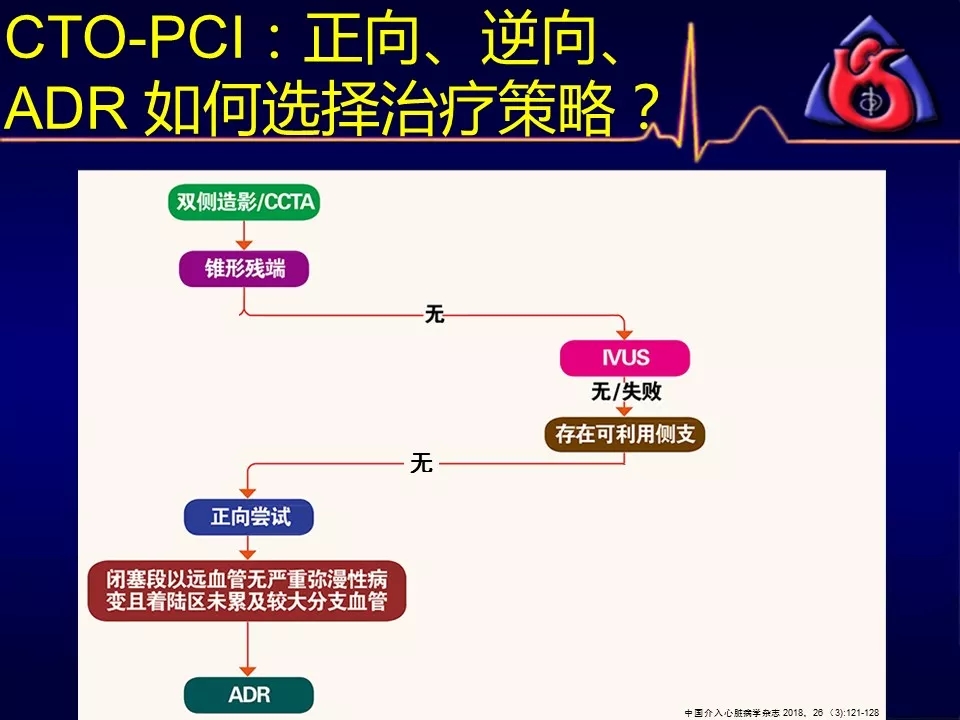

如何选择正向、逆向、IVUS指引及ADR技术?

别着急,葛雷教授带来动态幻灯版讲座:

《CTOCC CTO-PCI流程图精讲》

为您解答上述疑问